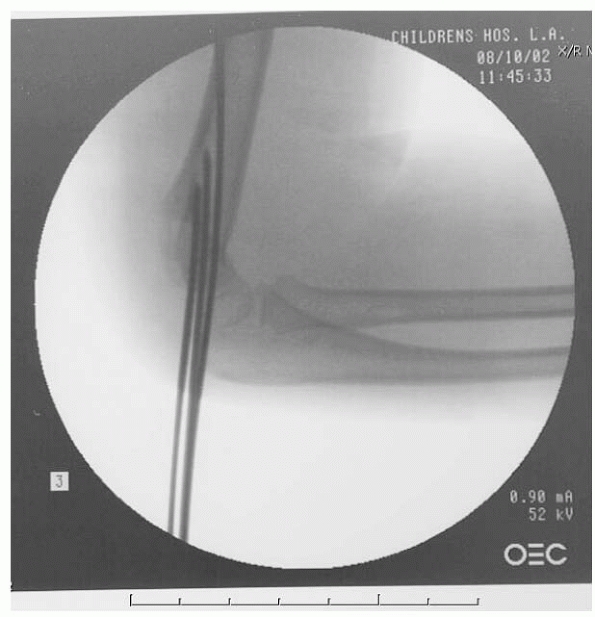

described closed reduction in 9 patients. Their technique involves

placing two K-wires into the distal fragment, reducing the fracture in

the AP plane, and verifying the reduction with fluoroscopy. Then the

fluoroscopy unit, rather than the arm, is rotated to obtain a lateral

view (Fig. 14-25). The fracture is reduced in

the sagittal plane, and the K-wires are driven across the fracture

site. All fractures treated with this technique united with no cubitus

varus, malunion, loss of motion, or additional operative treatment.

Because of the limited number of these multidirectionally unstable

fractures in their series, neither the need for open reduction nor the

true complication rates can be determined.